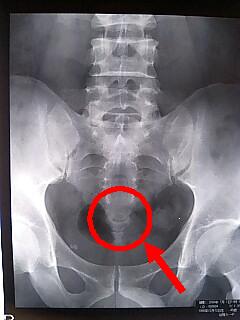

『ほねが折れてます

』という

キーホルダーが

あればいいのにー

見かけでは全く

健常者と変わらない

尾てい骨や肋骨を

骨折している人の為に

』のキーホルダーが欲しい